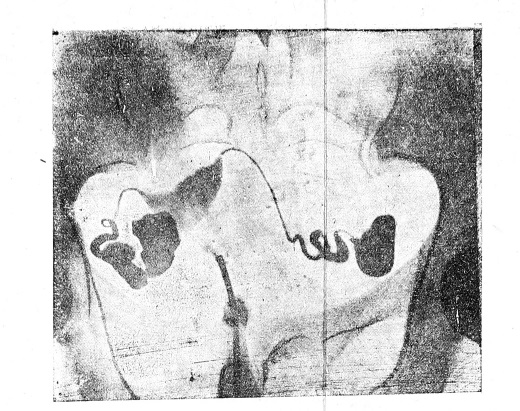

Наконец, среди нашего материала мы выявили также случаи редкой аномалии—полное разделение полости влагалища с наличием двух совершенно самостоятельных маток (рис. № 7). В каждое влагалище вдавалась самостоятельная portio vaginalis конической формы с хорошо проходимыми цервикальными каналами. Мы предварительно ввели катетер в цервикальный канал, находящийся в левом влагалище, и заполнили полость матки ок. 6 куб. см. иодипина, причем на снимке выявили сильно отклоненную влево полость, имеющую необычную грушевидную -форму. Из противоположной цервикальному отделу части матки отходила извивающаяся тонкая тень одной фаллопиевой трубы. В брюшной полости определялись шарики иодипина, следовательно труба оказалась проходимой. Затем, мы, не вынимая катетера из левого цервикального канала, вставили второй катетер в правый цервикальный канал и ввели вновь 6 куб. см. иодипина, после чего сделали второй снимок. На рентгенограмме мы определили сильно отклоненную вправо совершенно самостоятельную вторую матку—также с полостью грушевидной формы. Из аналогичного первой матке места отходила сильно извитая одна фаллопиева труба. В брюшную полость вновь проникло много иодипина в виде шариков частично, в виде расползшейся массы; таким образом, и правая труба оказалась проходимой. О толщине влагалищной перегородки можно судить по тени пинцета, захватившего эту перегородку по длине ее (рис. № 7).

Рис. 7